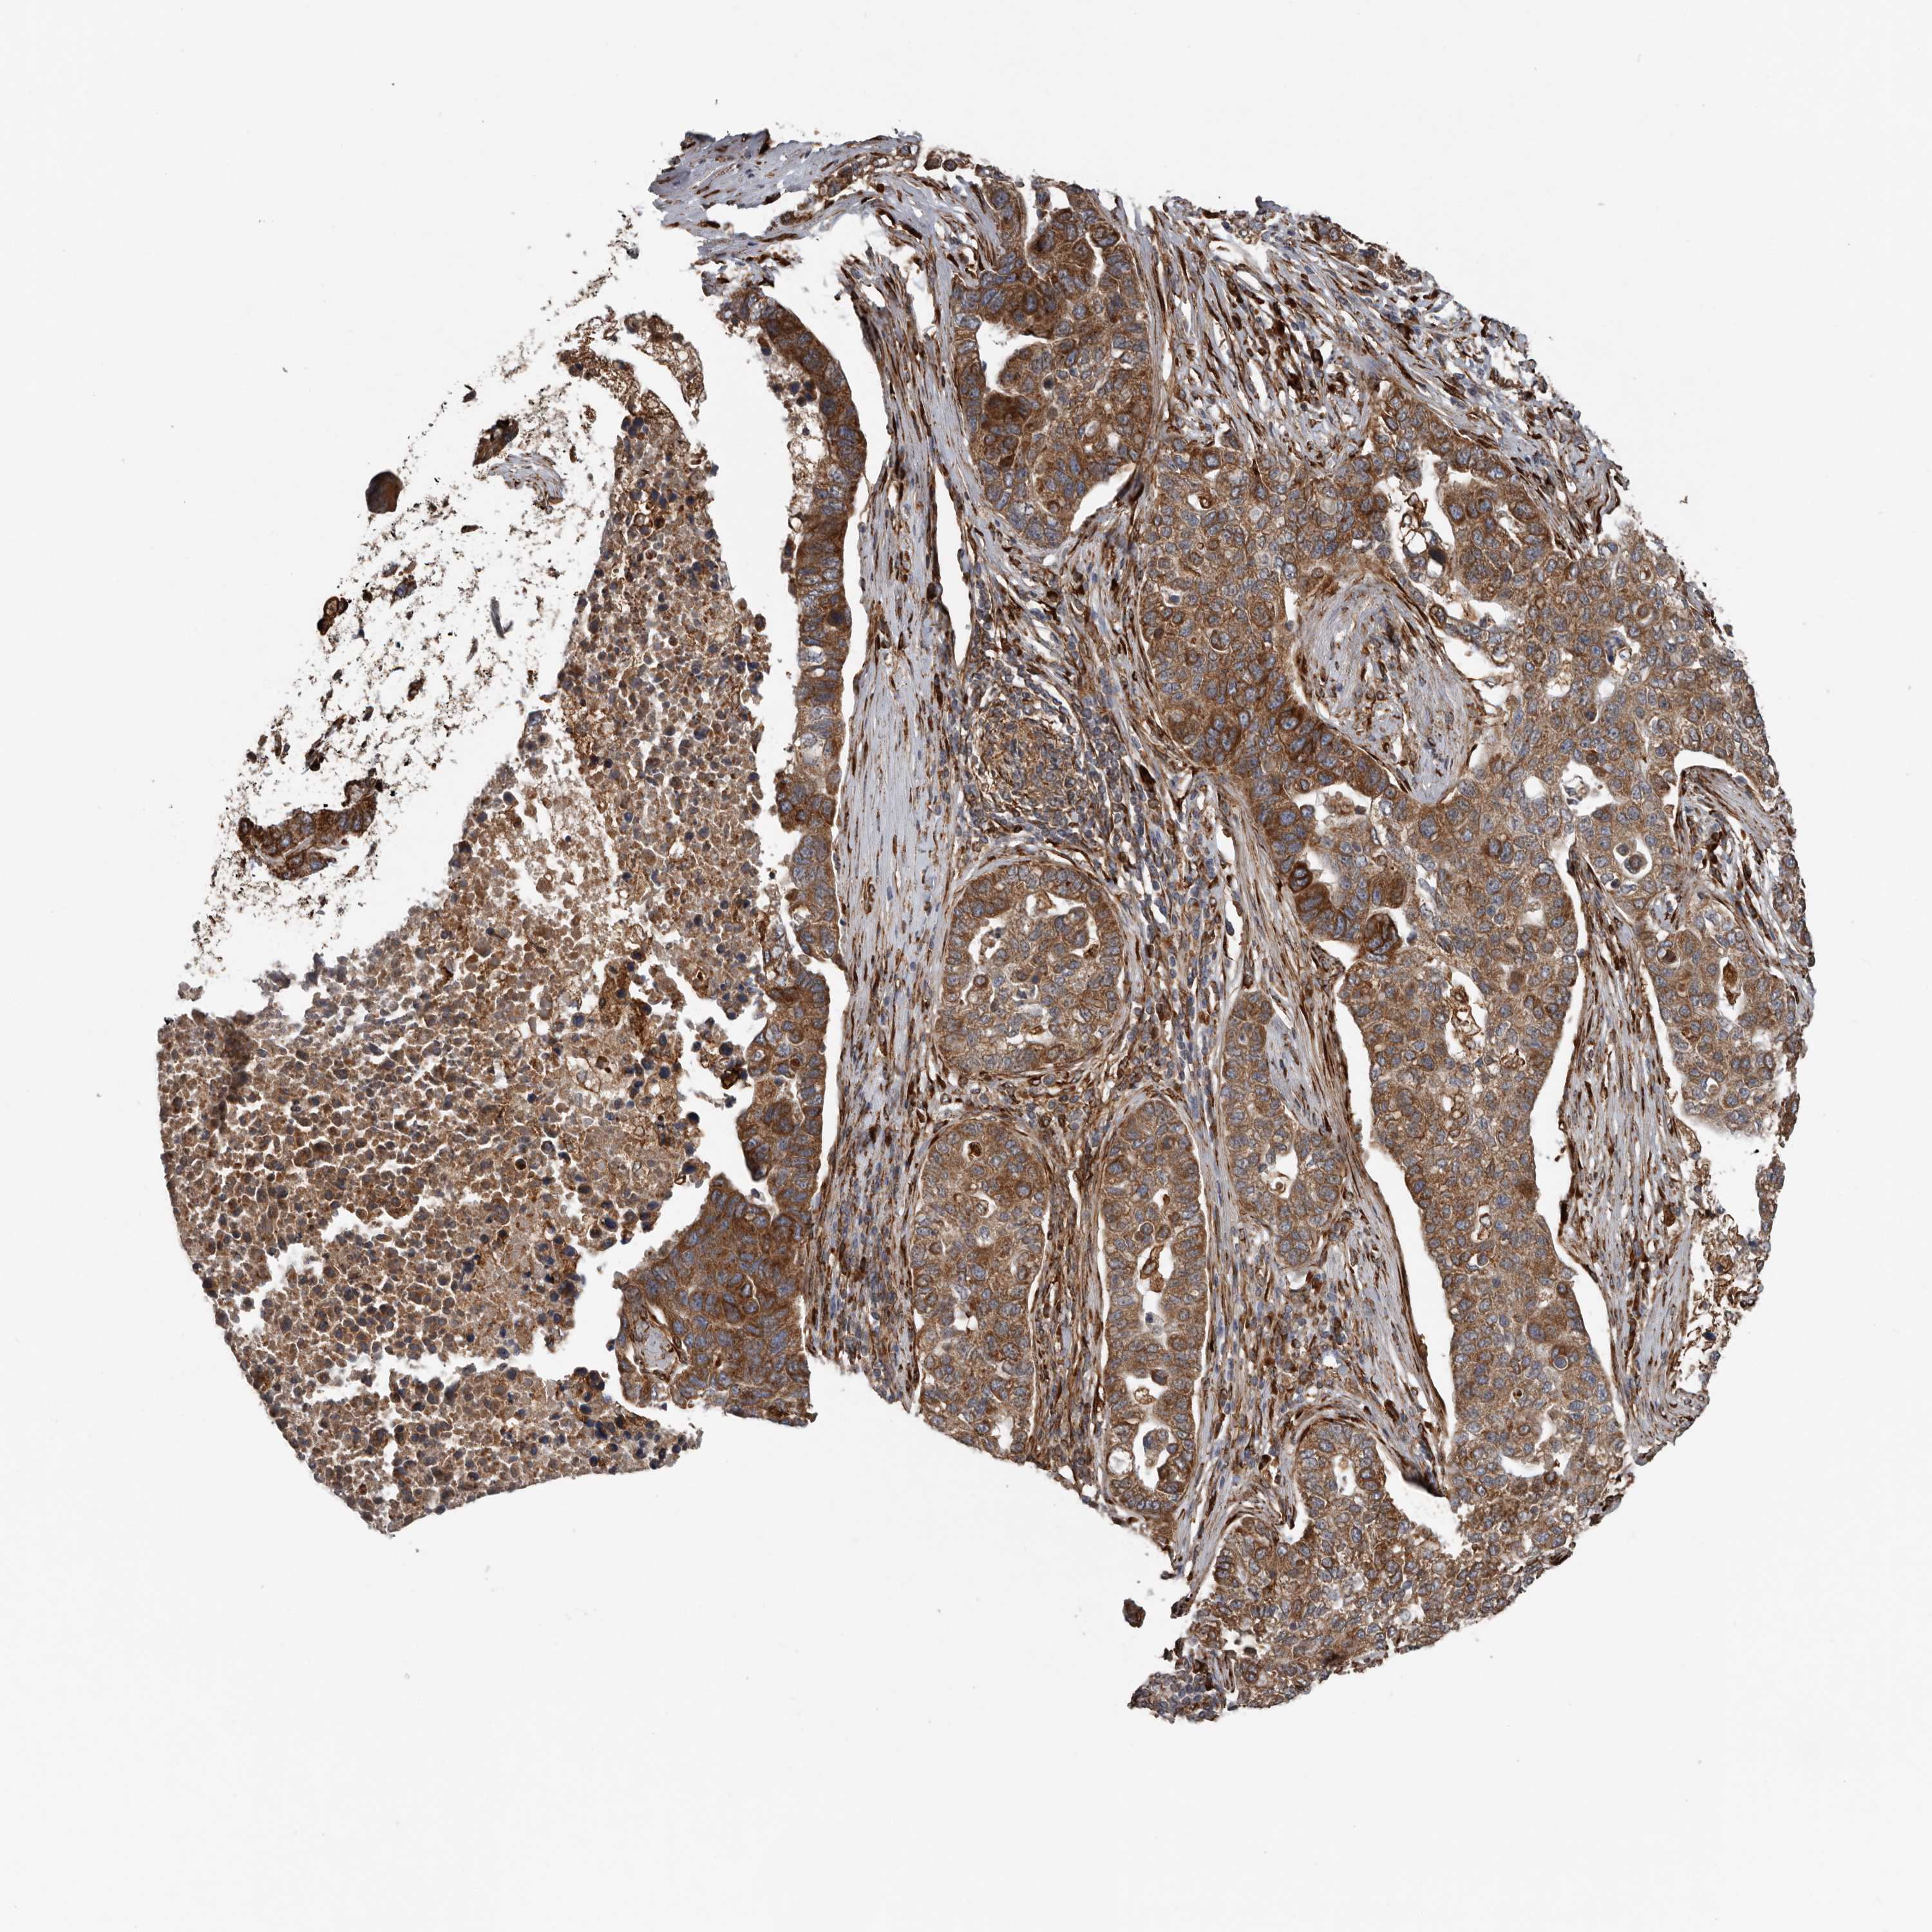

PANCREATIC CANCER - Protein expressioni

A mouse-over function shows sample information and annotation data. Click on an image to view it in a full screen mode. Samples can be filtered based on level of antibody staining by selecting one or several of the following categories: high, medium, low and not detected. The assay and annotation is described here.

Note that samples used for immunohistochemistry by the Human Protein Atlas do not correspond to samples in the TCGA dataset.

Antibody stainingi

Antibody staining in the annotated cell types in the current human tissue is reported as not detected, low, medium, or high, based on conventional immunohistochemistry profiling in selected tissues. This score is based on the combination of the staining intensity and fraction of stained cells.

Each image is clickable and will lead to virtual microscopy that enables deeper exploration of all samples and also displays staining intensity scores, fraction scores and subcellular localization as well as patient and tissue information for each sample.

Antibody HPA028355

Antibody HPA028357

Staining

High

Medium

Low

Not detected

Intensity

Strong

Moderate

Weak

Negative

Quantity

>75%

75%-25%

<25%

None

Location

Nuclear

Cytoplasmic/membranous

Cytoplasmic/membranous,nuclear

Adenocarcinoma, NOS